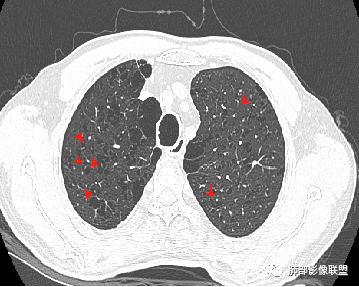

CT平扫示双肺弥漫分布大小不等囊状薄壁透光区,无内、中、外带分布差异,间质稍示增厚。拟LAM

中年女性育龄期妇女,咳嗽气喘,无吸烟史,有苯吸入史。影像:双肺弥漫均匀小囊腔,无明显分布优势,囊腔形态欠规则,壁薄,部分囊腔边缘血管征,伴双肺弥漫磨玻璃影,无结节,考虑lam,鉴别苯中毒肺损伤,囊腔多有分布优势,小叶中心分布为主,形态规整等

女,46,活动性气喘1年。苯吸入史半年。胸部CT:两肺弥漫囊腔,上至肺尖,下至肋膈角,形态类似小囊腔。考虑:LAM,鉴别LIP,BHD,PLCH等。

双肺弥漫大小不一薄壁含气囊腔,囊间肺组织正常,正常肺背景,肺尖肺底受累;青年女性,气喘,支持LAM

双肺多发大小相近的囊状影,分布趋势趋于一致,中年女性,考虑LAM。部分囊内见血管及分隔影,小叶中心性肺气肿代排

CT表现:双肺弥漫大小不等的薄壁囊腔,囊壁<2mm,外形规则,血管影多位于囊腔周围,囊腔之间肺组织正常,随着疾病进展到晚期,囊腔变大、增多,不可胜数,囊腔可融合成较大的囊,与肺气肿相似,形成间质性肺纤维化。部分病例可出现结节影。